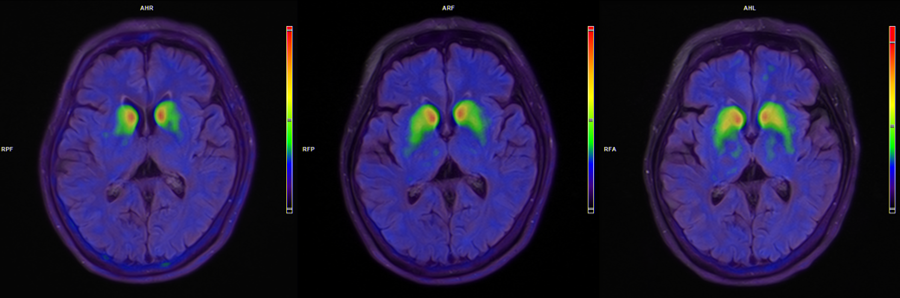

患者脑部术前、3个月、6个月的18F-FP-CIT PET图像